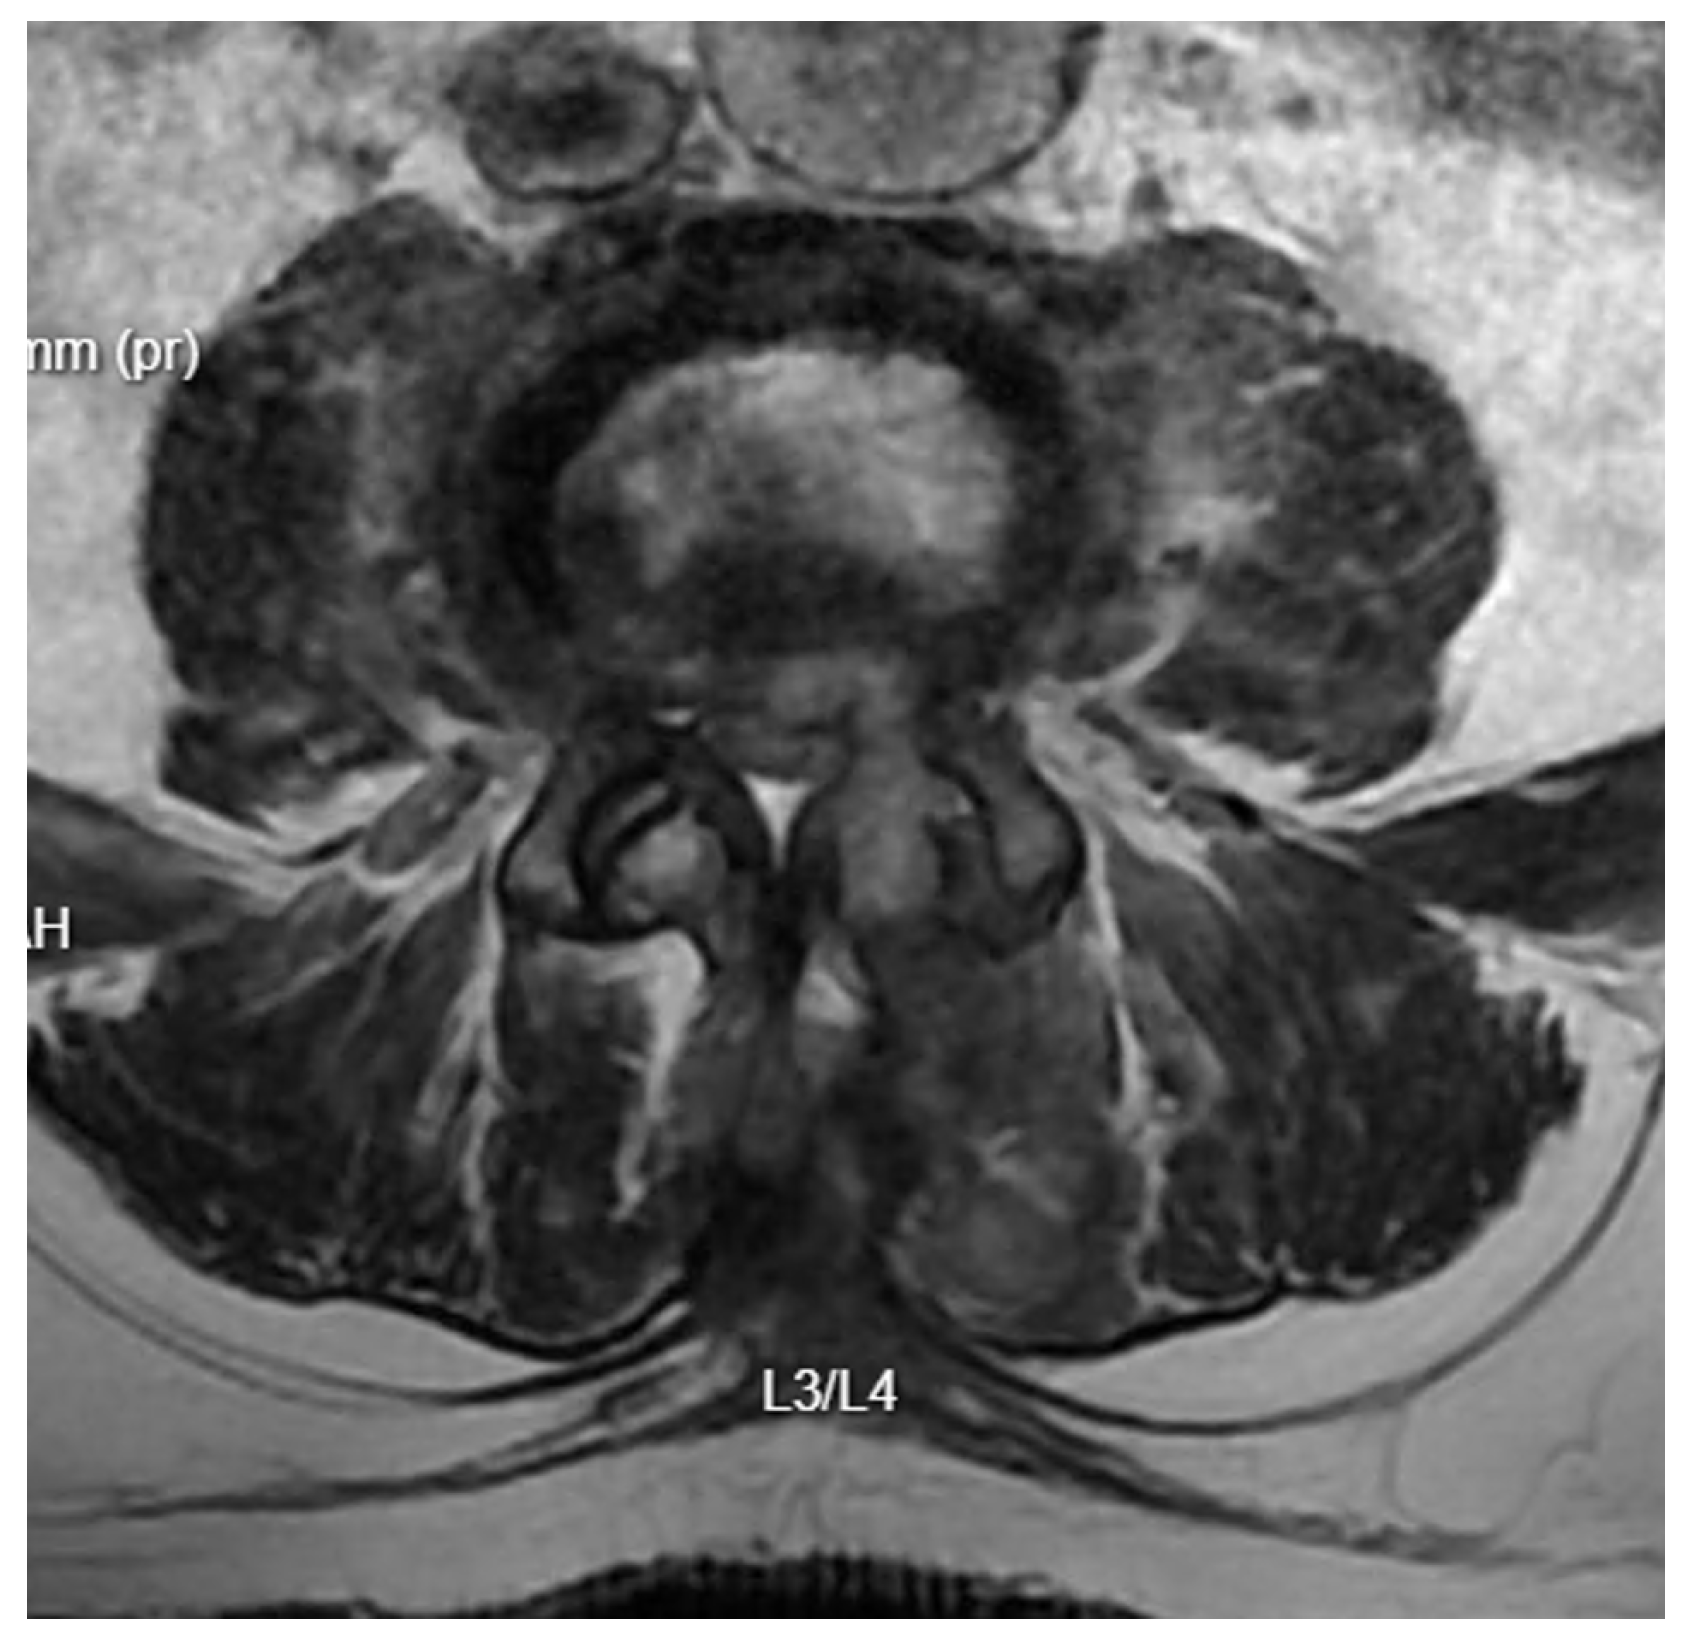

Patient Background: A 70-year-old male patient with a history of diabetes and chronic renal failure was scheduled for surgical treatment of discopathy at the L3/L4 level (Figure 6). The patient underwent microdiscectomy using a minimally invasive access retractor Spotlight (Johnson and Johnson, New Brunswick, NJ, USA).

Further Intervention: Another MRI confirmed that despite extensive decompression, significant narrowing persisted at the operated level, with a markedly increased T2 signal in the disc space (Figure 7). A subsequent endoscopic transforaminal approach was employed. Inflammatory disc material and granulation tissue from the spinal canal were removed. Post-operative MRI showed a satisfactory degree of decompression of the canal. The patient was mobilized and transferred to the nephrology department due to further deterioration of renal function.

Figure 7. T2 axial MRI image at the L4/L5 level following previous open surgical treatment.